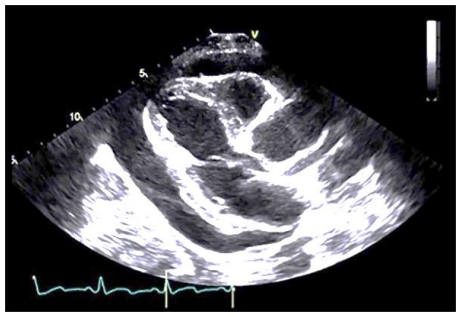

Homem de 78 anos, 75kg e 1,70m, hipertenso e diabético, se apresenta na emergência cardiológica com dor torácica forte, sendo indicada cineangiocoronariografia. Exames laboratoriais evidenciaram ureia de 200mg/dL-1, creatinina de 3,2mg/dL-1, potássio de 5,5mEq/L-1 e hemoglobina de 9,2g/dL-1. O ecocardiograma revela a seguinte imagem: